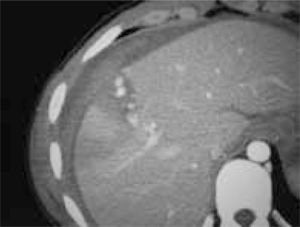

Es una herramienta importante en el manejo del trauma abdominal y abdominopélvico cerrado. Se encuentra reservada para los pacientes hemodinamicamente estables y que puedan ser trasladados al tomógrafo, y tolerar el estudio (3, 9, 10). Se debe utilizar medio de contraste oral e IV (3, 9, 10). La TAC puede determinar la presencia de lesiones en órganos sólidos, líquido intrabdominal, sangre, aire y lesiones en los órganos retroperitoneales, los cuales pueden haber sufrido con el trauma y no provocan hemoperitoneo, por lo que no son detectados con el ultrasonido (3, 10), como también mostrar la extensión de la lesión en estructuras como el bazo e hígado, así como determinar la extravasación de contraste, que implica sangrado activo (3, 9). Debido a estas características, la TC es muy útil para decidir el manejo terapéutico de la lesión (3, 8). De todas maneras el valor de la administración de contraste oral para el diagnóstico de perforación de víscera hueca es dudoso, y se encuentra asociado al riesgo de broncoaspiración, por lo que no debe realizarse de rutina (3). La TC tiene una sensibilidad de 92 a 98% y una especificidad de casi 99% en la detección de lesiones de órganos sólidos (3). No detecta lesiones de diafragma, intestino y algunas de páncreas (3, 9). Debe tomarse en cuenta la experiencia del radiólogo que interpreta el examen (8).

Figura 4 Trauma hepático. Figura 5 Trauma renal. Figura 6 Lesión del sistema colector con urinoma de la pared.